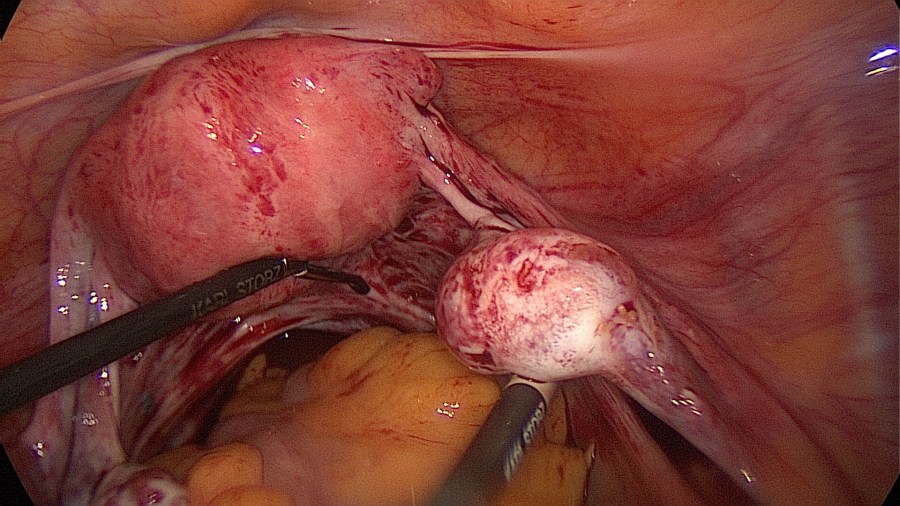

Visualize the ectopic pregnancy.

Linear salpingotomy: open the tube directly over the tubal pregnancy with a straight incision made with a monopolar needle (Taran, F-A et al., 2015).

Grasp the contents with an atraumatic grasper and expell the tubal pregnancy en bloc. Failure to do so may increase risk of persistent ectopic tissue. Alternatively this may be performed with suction or aquadissection.